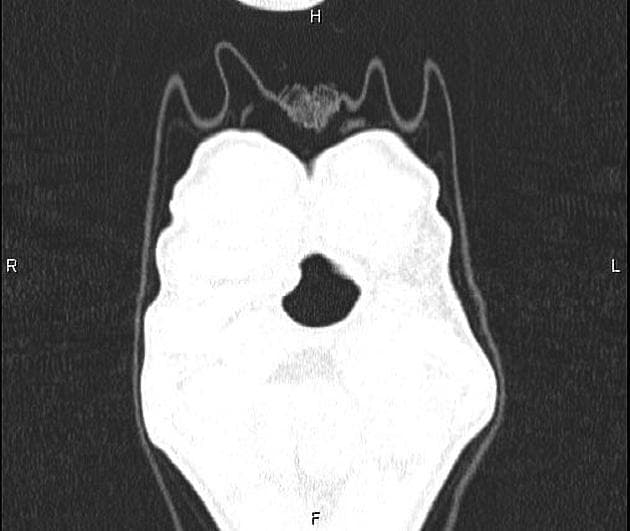

Series (10)

Axial Gradient Echo

- Có các ổ dịch ngấm thuốc viền (peripherally enhancing collections) xung quanh khớp cùng đòn mỏm cùng phải.

- Các ổ này đi kèm với tín hiệu bất thường ở tủy xương trong mỏm cùng (acromion) và đầu xương đòn (distal clavicle), cùng với các ổ ăn mòn vỏ xương (cortical erosions) ở xương đòn.

- Ngoài ra, thấy nhiều ổ dịch ngấm thuốc viền kích thước khác nhau nằm trong mô dưới da và các mặt phẳng cơ.

- Các ổ này lan vào các cơ thang (trapezius), cơ delta (deltoid) và cơ ngực lớn (pectoralis), đi kèm tín hiệu bất thường và ngấm thuốc thì tĩnh mạch cửa (post-contrast enhancement) ở các cơ lân cận và mô dưới da phía trên.

- Trong trường hợp này, sự hiện diện của các ổ dịch ngấm thuốc viền tập trung quanh khớp cùng đòn mỏm cùng, kết hợp với bất thường tín hiệu tủy xương và các ổ ăn mòn vỏ xương ở xương đòn và mỏm cùng, hỗ trợ chẩn đoán viêm khớp nhiễm trùng. Viêm tủy xương kèm theo (osteomyelitis) cũng là một khả năng rất cao.

- Các ổ dịch lan rộng trong cơ và dưới da, ảnh hưởng đến các cơ thang, cơ delta và cơ ngực lớn, biểu hiện cho sự lan rộng của nhiễm trùng với sự hình thành nhiều ổ áp xe – đây là một biến chứng đã được ghi nhận trong nhiễm trùng kéo dài hoặc tiến triển nhanh.

- Đã thực hiện dẫn lưu ổ dịch dưới hướng dẫn hình ảnh, thu được khoảng 400 mL dịch mủ, xác nhận bản chất nhiễm trùng của tổn thương.